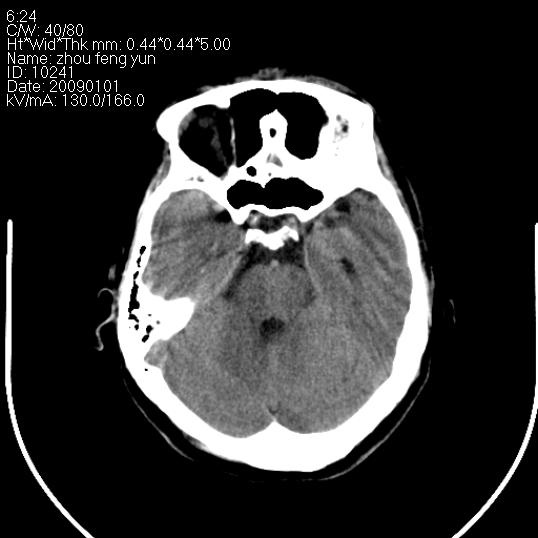

以下是引用hhcckk在2009-1-1 16:39:00的发言:[br]胼胝体嘴、膝部及部分体部发育不全,为囊状影替代,两侧侧脑室分离,脑室后角扩张[br][br]诊断:胼胝体发育不良[br][br]胼胝体发育不良(dysgenesis of the corpus callosum)是最常见的颅脑畸形,是胚胎期背部中线结构发育不良的一种形式。主要包括胼胝体缺如和部分缺如。胼胝体发育不良还可合并其他畸形,如胼胝体脂肪瘤、蛛网膜囊肿、脑膨出、chiari畸形、灰质异位症、脑回畸形等。[br][br]ct诊断要点:[br]1. ct横断扫描可见两侧侧脑室明显分离,脑室后角扩张,形成典型的蝙蝠翼状侧脑室外形。[br]2. 第三脑室扩大并向上插入两侧脑室体部之间,严重者第三脑室可上移到两侧大脑半球纵裂的顶部。在ct冠状扫描位显示更清。[br]4. 胼胝体畸形常伴有脂肪瘤,可测到其特征性脂肪密度。部分脂肪瘤的边缘可出现线样钙化[br]